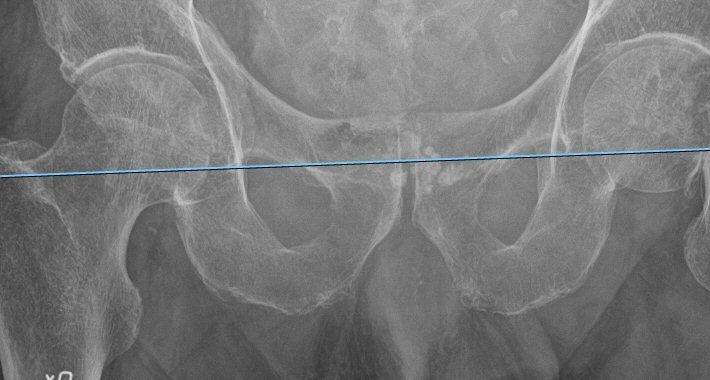

Referenslinje lagd med teardrops nedre kanter som referenspunkter

- Notera att benlängdsuppskattningen påverkas av om bäckenet är tippat åt något håll, eller om endera femur står add- eller abducerat. Lägg därför referenslinjen även vid de andra referenspunkterna och försök analysera hur bäckentippning och/eller femurposition påverkar uppmätt benlängd.

- Lägg den horisontella referenslinjen mitt i rotationscentrum på den friska sidan. Det underlättar om man har kvar offset-mätningens kula där centrum är markerad.